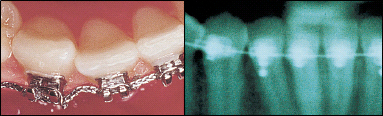

Die Zahnpflege ist bei einer Behandlung mit fester Zahnspange besonders wichtig und leider etwas zeitaufwendiger, da alle Zahnflächen rund um das Bracket (aufgeklebter Teil der Zahnspange) richtig gereinigt werden müssen. Speisereste bleiben an der festen Zahnspange leichter haften und müssen gründlich entfernt werden. Sonst entsteht wie überall an den Zähnen auch ohne feste Zahnspange ein Loch. Die weißen Verfärbungen, die um das Bracket entstehen können, sind Vorstufen von Karies und gehen auch nach der Entfernung der Apparatur nur selten wieder weg. Daher wird der Kieferorthopäde wie auch der Zahnarzt großen Wert auf eine gute Mundhygiene legen und mit den Patienten üben, wenn die Zahnpflege nicht ausreichend ist.

Das Zähneputzen und auch die Verwendung geeigneter Hilfsmittel sind nach jeder Mahlzeit Pflicht. Zusätzlich kann es empfehlenswert sein, die Zähne zur Vorbeugung (Prophylaxe) regelmäßig professionell vom Zahnarzt oder Kieferorthopäden reinigen zu lassen. Zum Ritual werden sollte das Zähneputzen nach jeder Haupt- und Zwischenmahlzeit – und zwar mindestens drei Minuten. Jeder Zahn muss von allen Seiten gründlich gereinigt werden. Das bedeutet: von außen und innen, inklusive der Zwischenräume, sowie die Kauflächen. Mit elektrischen Zahnbürsten geht man genauso vor wie mit normalen Zahnbürsten. Genauso wichtig wie der richtige Umgang mit der Zahnbürste ist auch der Einsatz spezieller Bürsten, Zahnzwischenraumbürsten und Mundduschen, um die Brackets rundum sauber zu halten. Mit den speziellen Zahnbürsten und Zahnzwischenraumbürsten lässt sich gefährlicher Zahnbelag entfernen. Auch die regelmäßige Verwendung von Fluoridgel kann die Zähne stärken und sie so zusätzlich vor Karies schützen.